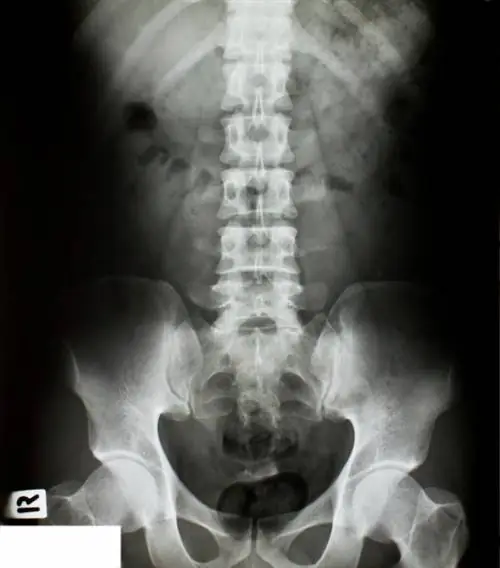

Хроническая боль в пояснице - это серьезная проблема со здоровьем, которая затрагивает 85% американцев и ежегодно обходится экономике США примерно в 100 миллиардов долларов. Боль часто исходит от одного из 23 дисков, которые имеют решающее значение для движения и расположены между позвонками позвоночника человека. Со временем или из-за чрезмерного стресса или травмы эти диски начинают дегенерировать или даже грыжи. Это распространенные источники хронической боли в пояснице.

Эта новая концепция может быть многообещающей, учитывая, что наиболее распространенным хирургическим лечением хронической боли в пояснице является спондилодез. В хирургии слияния дегенеративный диск заменяется костью, чтобы срастить соседние сегменты, что должно предотвратить боль, вызванную движением. Однако удовлетворенность пациентов хирургией слияния составляет менее 50%. Новая хирургическая концепция, разработанная командой BYU, включает в себя соответствующий механизм, который обеспечивает естественное движение позвоночника и направлен на восстановление функции здорового диска. Податливые механизмы не имеют суставов и состоят из эластичных структур, которые используют гибкость для создания движения. Примерами совместимых механизмов могут быть пинцет, кусачки для ногтей или лук и стрелы.3